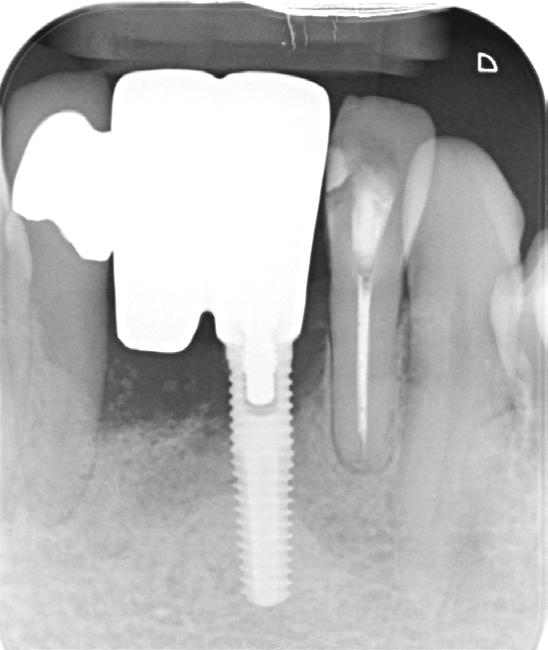

A 67-year-old gentleman was referred with the chief complaint of having discomfort in the area of implant supported bridge (31 and 41). The clinical and radiographic examination revealed presence of inflammation, lack of attached mucosa, as well as progressive bone loss since installment of the implant. The diagnosis of active periimplantitis #31 implant was made. Due to the patient's satisfactory plaque control and low levels of full mouth plaque score, a surgical management was indicated. This included a surgical debridement, partial implantoplasty in the exposed part, as well as soft tissue conditioning in order to increase the band of attached mucosa in the form of free gingival grafting. This treatment in combination with regular CIST (Implant Supportive Therapy) resulted in elimination of the inflammatory component (BOP and progressive bone loss) as well as facilitation of the self-performed plaque control via tissue graft.

1. Radiographic view of implant in 31 position with marginal bone loss.